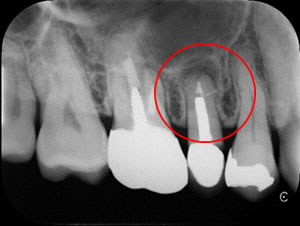

先日歯の激痛と打診痛がひどくお見えになった患者さんです。レントゲン検査で根の先端が破壊されていることが解りました。またかなり大きく深いポストがはいっていて、健康な歯質も少なくかなり難しいケースです。

治療前